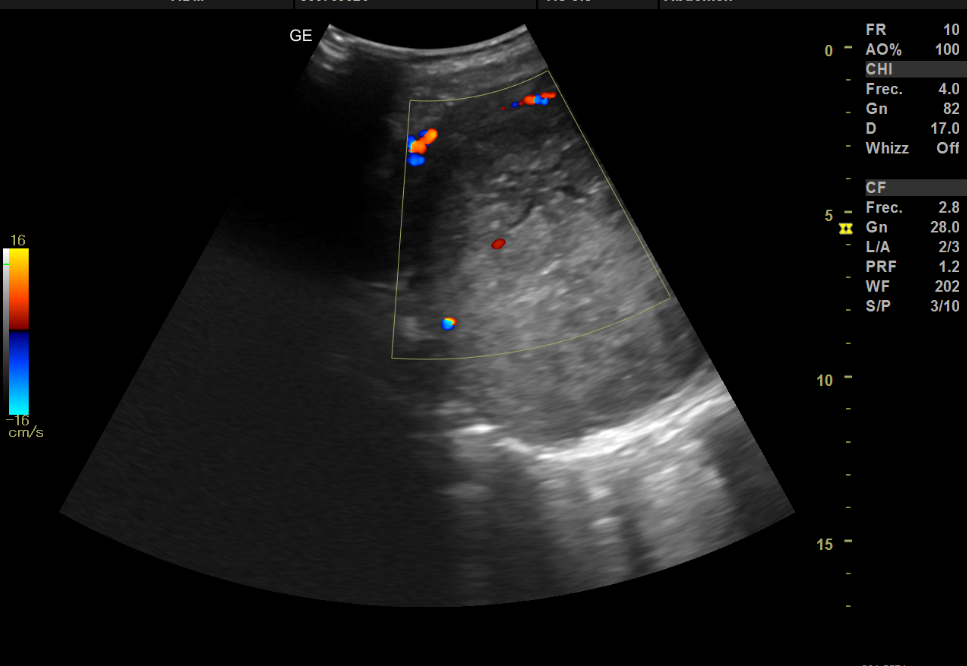

Se le realiza a la paciente ecografía abdominal con sonda cónvex, donde se objetiva en la zona anteriormente mencionada masa de unos 138 mm en su eje longitudinal y 108x90 mm en un corte transversal, no pudiendo precisar con exactitud el origen de la misma. Al aplicar el Doppler color se observa una captación periférica.